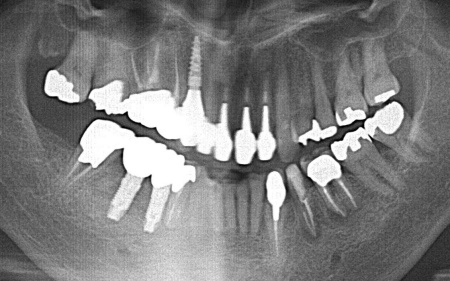

歯やあごの骨の状態を詳しく調べるためレントゲン検査を行った結果、右下の奥歯2本(第2小臼歯、第1大臼歯)は、歯根が縦方向に割れている可能性が高いと考えられました。 しかし、レントゲン画像だけでは歯根の状態を正確に判断することはできません。 歯根が割れている場合、細菌感染が進行して歯ぐきの炎症が広がったり周囲の歯やあごの骨にまで影響を及ぼしたりする可能性があります。 以上のことから、歯を温存することは難しいため抜歯が必要と診断しました。 |

| 行ったご提案・治療内容 | 診断結果を丁寧に説明したうえで、右下奥歯2本の抜歯を提案したところ同意いただきました。 併せて抜歯後に歯を補う方法として、以下2つの選択肢をお伝えしました。 ①前後の歯を削って橋のようにつなげた被せ物で歯を補うブリッジ治療 ②あごの骨に人工の歯根を埋め込み、その上に人工歯を取り付けるインプラント治療 それぞれの特徴や注意点について説明したところ、患者様は②のインプラント治療を希望されました。 まず右下奥歯2本の抜歯を行い、その後、約3ヶ月間歯ぐきや骨が十分に回復するのを待ちました。 |

治療前